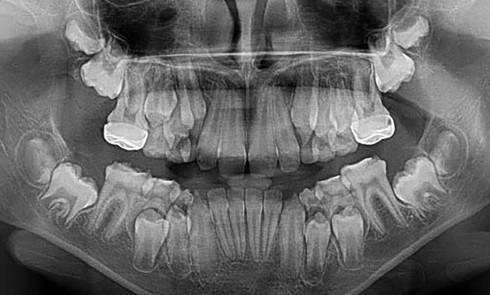

Article réservé à nos abonnés Intérêt de l’avulsion précoce des canines temporaires maxillaires pour une évolution optimisée des canines permanentes

Orthopédie dento-faciale Le service d’Orthopédie dento-faciale est composé actuellement de 10 enseignants qui constituent une équipe dynamique et polyvalente (1 PU-PH,...